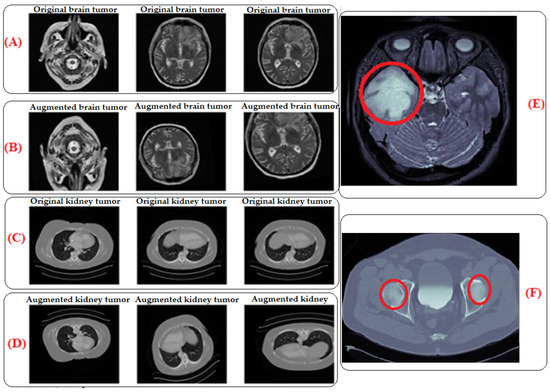

By subjecting the model to a wider range of variations and scenarios, traditional data augmentation techniques were utilized to expand the size and diversity of our training dataset and improve the model’s robustness [6,50]. This entails using different transformations, such as flipping, shifting, rotating, or zooming, on the current data to produce new training examples that are marginally different from the initial ones, as Table 2 illustrates. By adding more data, the model’s sensitivity to noise or tiny changes in the input data is reduced, improving the generalization performance, as seen in Figure 2. The area circled in the red color shows the tumors. The images in (E) for the brain and (F) for the kidney are the zoomed-in images that show the areas where the tumors are located. (E) represents a zoomed-in view of an augmented brain tumor image and allows for a detailed examination of the specific region where the tumor is located. This zoomed-in view provides insights into how the augmentation process affects the detailed features of the tumor in the image. Similar to part E, (F) shows the augmented kidney tumor image (MRI), which contributes to the diversity of the training dataset for kidney tumor images. (A) The original brain tumor image (MRI) represents the original MRI scan focused on the brain, specifically showcasing a tumor. It is the unaltered, initial image used in the training dataset. (B) The augmented brain tumor image (MRI) corresponds to the image of the brain tumor that underwent traditional data augmentation techniques. These techniques involved applying various transformations like flipping, shifting, rotating, or zooming to create slightly different versions of the original image. Part B displays the augmented version, contributing to an expanded and more diverse training dataset. (C) The original kidney tumor image (MRI) represents the original unaltered MRI scan focused on the kidney, specifically showcasing a tumor. (D) The augmented brain tumor image (MRI) corresponds to the image of the kidney tumor that underwent traditional data augmentation techniques.